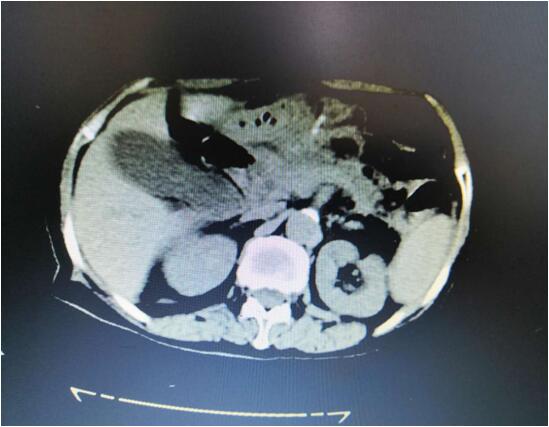

患者B,女,51歲,因牙齦出血1年入院,入院診斷為:乙肝,肝炎后肝硬化,門脈高壓癥,巨脾,脾亢,白細(xì)胞、血小板減少,中度貧血。5年前,曾在外院行介入脾栓塞術(shù),脾臟不僅沒有縮小,反而越來越大,脾下緣已經(jīng)超過腹部正中線、抵達(dá)臍部,就像幾個月“身孕”的婦女,給病人帶來巨大身心負(fù)擔(dān)。

(術(shù)前腹部CT顯示巨脾)